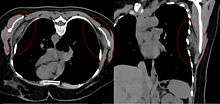

Bilateral elastofibroma dorsi in native computed tomography: left image axial in prone position (for biopsy), right image oblique coronal view.

By computed tomography, there is a poorly circumscribed, heterogeneous soft tissue mass, with a signal intensity similar to skeletal muscle. The fact that the lesion may be bilateral, helps eliminate a sarcoma from further consideration.[4] At US, elastofibromas are depicted deep to the musculature as a multilayered pattern of hypoechoic linear areas of fat deposition intermixed with echogenic fibroelastic tissue.[5] The mass often protrudes from the subscapular region upon shoulder abduction, allowing better delineation of the finding.[6]